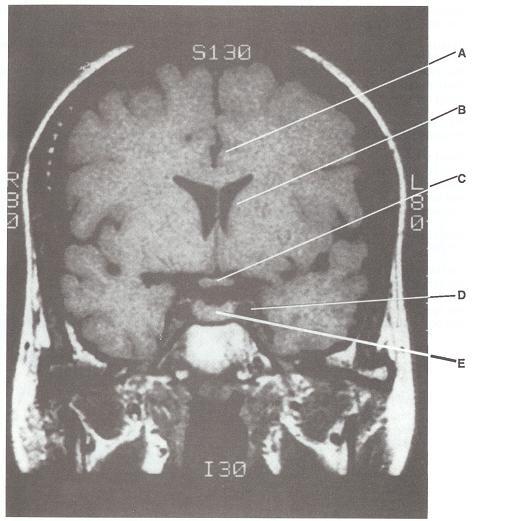

Match the descriptions in items 6-10 with the appropriate lettered structure shown in the Tl-

weighted magnetic resonance image (MRI) of the coronal section of the brain.

1. Lies within the cavernous sinus

2. Lies within the sella turcica

3. Is part of the striatum

4. Is part of the limbic lobe

5. Lies within a cistern

6-D. The carotid artery lies within the cavernous sinus, in company with CN III, CN IV, CN

V-l, CNV-2, and CNVI.

7-E. The hypophysis (pituitary gland) is found in the hypophyseal fossa of the sella turcica.

8-B. The caudate nucleus is part of the striatum.

9-A. The cingulate gyrus is part of the limbic lobe.

10-C. The optic chiasm lies within the chiasmatic cistern.